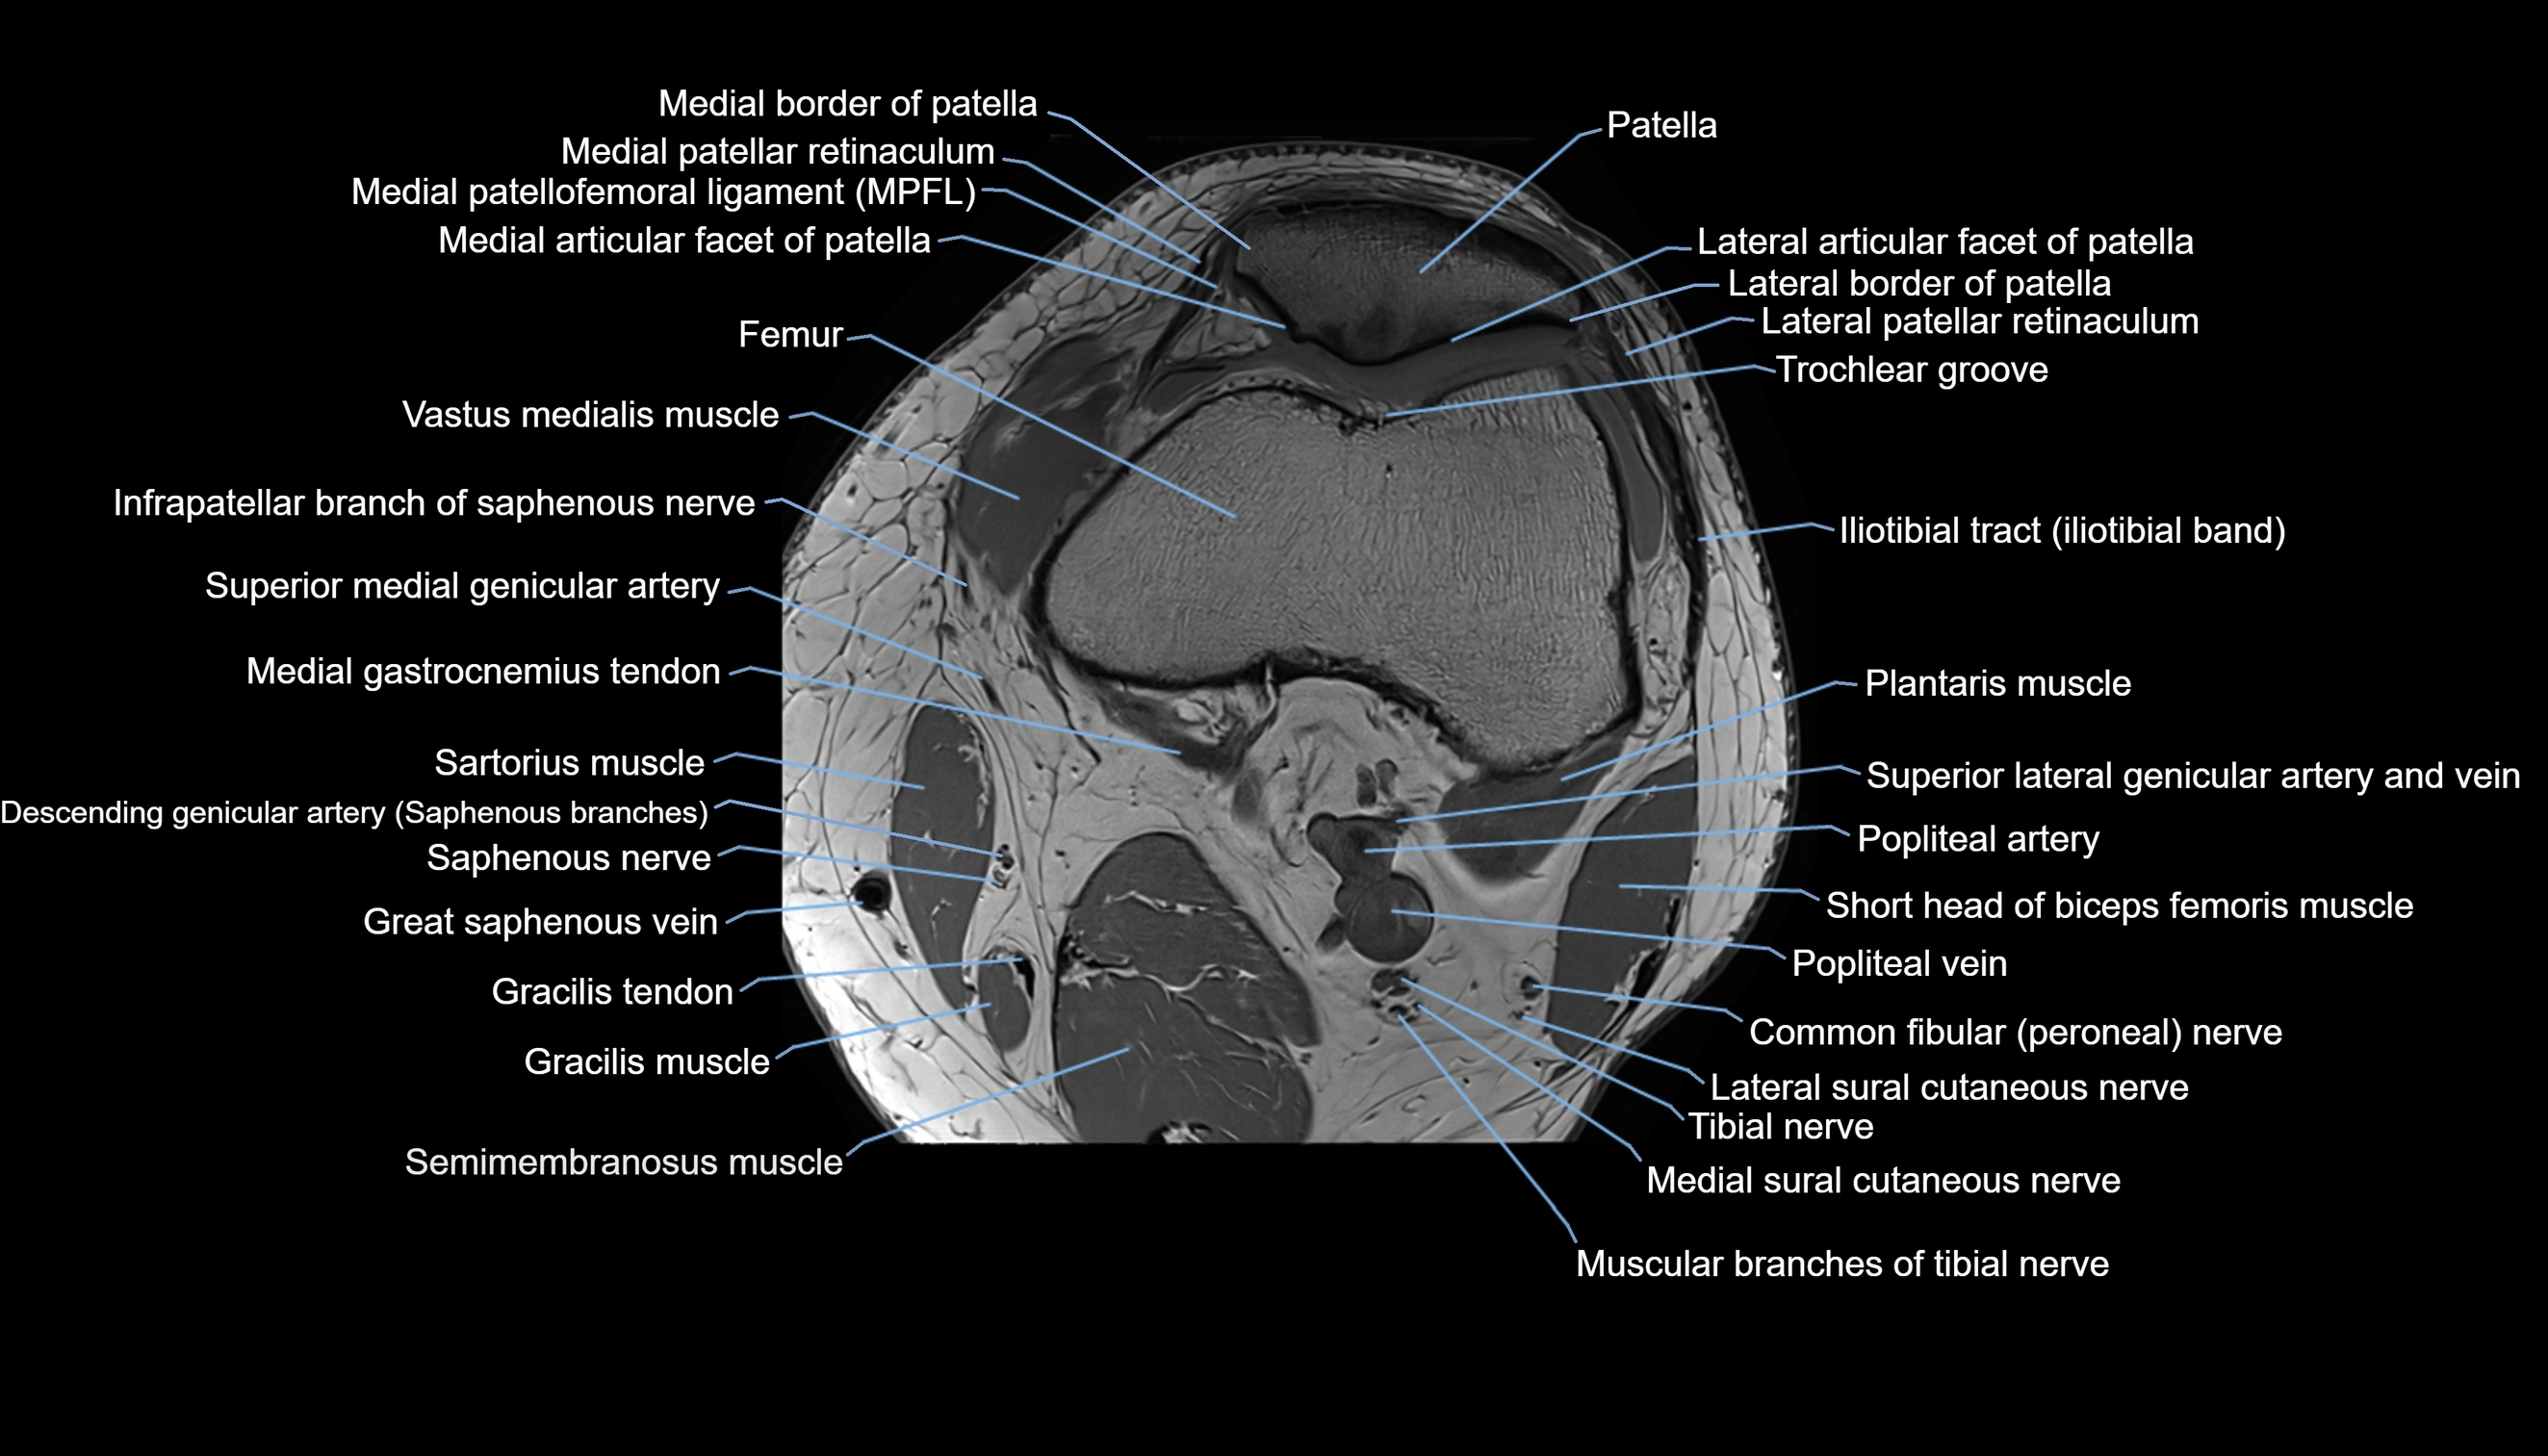

- Lateral articular facet of patella

- Lateral border of patella

- Lateral patellar retinaculum

- Lateral patellofemoral ligament

- Medial articular facet of patella

- Medial border of patella

- Medial patellar retinaculum

- Medial patellofemoral ligament

- Patella

- Trochlear groove